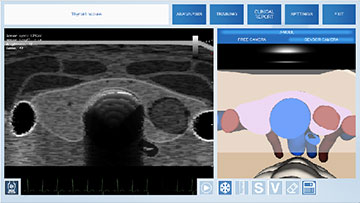

Симулятор ультразвуковой диагностики MedVision SonoVision

Виртуальный симулятор ультразвуковых исследований (УЗИ) SonoVision – обучающий тренажер на единой платформе обеспечивающий освоение основных навыков проведения ультразвукового исследования, понимание и идентификацию различных заболеваний и патологии внутренних органов человека.

SonoVision – симулятор ультразвуковой диагностики является инструментом для профессионального изучения медицины. Это виртуальный симулятор для отработки навыков ультразвуковой диагностики. Он используется как студентами, так и практикующими специалистами в клиниках и больницах. Симулятор ультразвуковой диагностики – прекрасное дополнение к традиционному обучению и повышению квалификации медицинского персонала.

Новое поколения симулятора УЗИ гарантирует высочайший уровень детализации внутренних органов, а работа с анатомически корректным манекеном обеспечивает реалистичные тактильные ощущения и визуальную картину при выполнении вмешательств. В симуляторе реализовано более 40 клинических сценариев.

Модуль по УЗИ щитовидной железы

- Обучающий модуль по ультразвуковому исследованию щитовидной железы